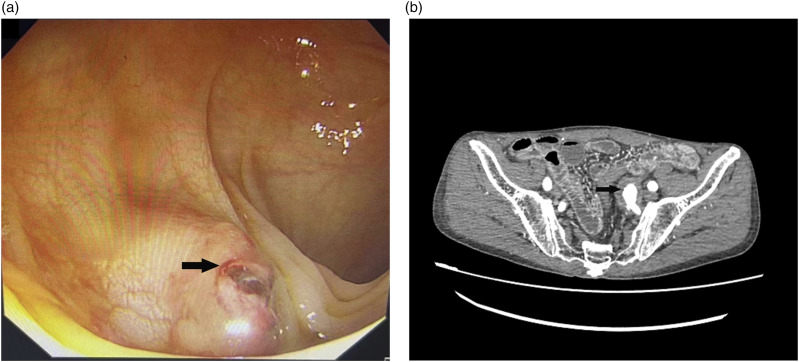

Primary aortoenteric fistula is a rare entity with high mortality. Depending on the location of the fistula, primary aortoenteric fistulas may lead to upper or lower gastrointestinal hemorrhages. The majority of primary aortoenteric fistulas are associated with atherosclerosis or aneurysms of the aorta, without any previous aortic procedure. Local inflammation, compression, or erosion may lead to rupture of the aneurysm. Owing to difficulties in immediate and correct diagnosis, effective treatment of primary aortoenteric fistulas is often delayed, leading to almost 100% mortality in untreated patients. Here, we report a case of a repetitive mass of lower gastrointestinal hemorrhage due to a primary internal iliac arterial-sigmoid colon fistula. Finally, the patient was managed successfully through endovascular coil embolization.